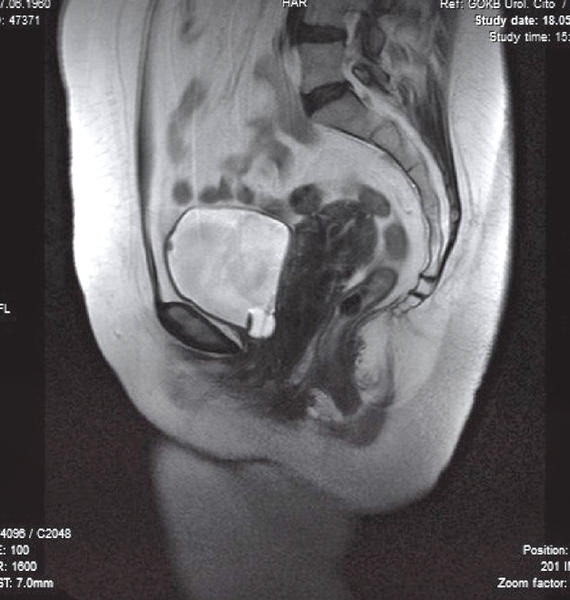

МРТ мочевого пузыря – точная диагностическая процедура, в ходе которой исследуется мочеполовой орган. Методика является неинвазивной, безболезненной и абсолютно безопасной для пациента. В ходе магнитно-резонансной томографии проверяется не только мочевой пузырь, но и все органы малого таза.

Для повышения точности исследования существует МРТ мочевого пузыря с контрастированием. Процедура предусматривает введение контрастного препарата внутривенно, после чего врач может выявить и оценить даже самые незначительные изменения. Кроме того, контрастирование обеспечивает полное отсутствие артефактов на снимках.

Результатом диагностики служат снимки, где обследованная область визуализируется послойно, то есть по срезам. Эти срезы имеют толщину всего в несколько миллиметров. На основе полученной информации можно даже создать трехмерную модель обследованного органа. Занимает диагностика в среднем полчаса. При использовании контрастного вещества процедура выполняется дольше.